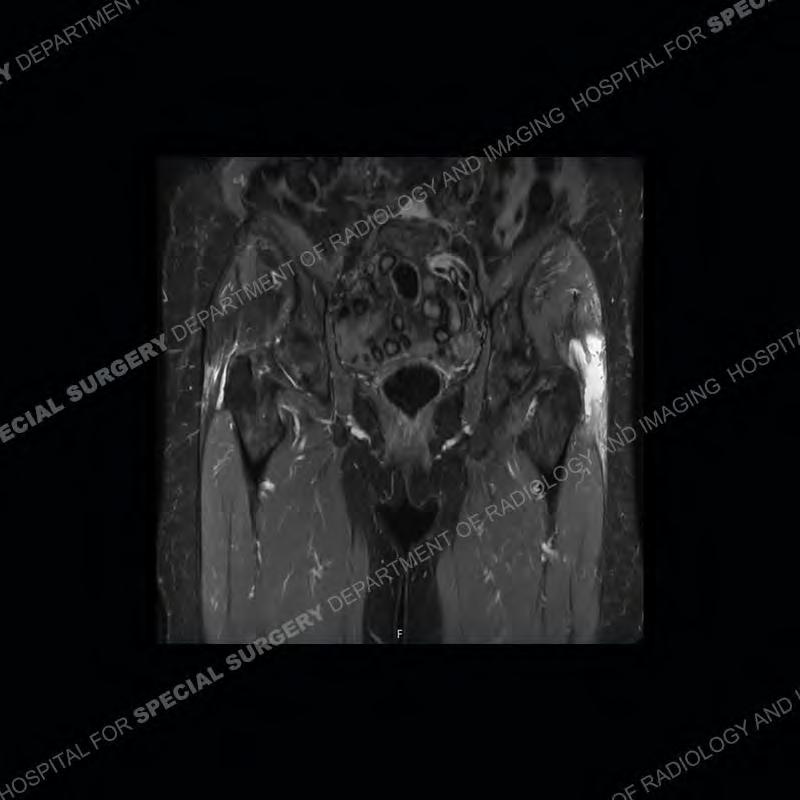

The radiograph is not particularly contributory in this case. The MRI demonstrates markedly abnormal architecture of the gluteus minimus and anterolateral band of the gluteus medius. Portions of the tendons are high signal, portions are highly attenuated, and portions are disrupted. A large, complex fluid collection is present in the adjacent soft tissue.

Diagnosis: Gluteal Tendinosis and Disruption with Complex Trochanteric Bursal Collection

Not as much of a diagnostic dilemma as many of the other cases shown but just a nice example of the pathology seen of the gluteal tendons and a cause of trochanteric pain. Although, frequently thought of in isolation, trochanteric bursitis or bursal thickening is much more commonly a reactive change to underlying pathology of the subjacent gluteal tendons. The gluteus medius is divided into a posterior band and an anterolateral band. Tendinosis and partial tearing very commonly will involve the gluteus minimus and especially the more posterior fibers and then propagate into the anterior lateral band of the gluteus medius. Involvement of the posterior band of the medius is much less common and engenders a marked degree of functional impairment.

The bursae about the greater trochanter can be a little bit confusing especially given the terminology. Trochanteric bursitis is implied to mean the subgluteus maximus bursa which is present deep to the maximus and just lateral/superficial to the trochanter. That is the bursa involved in this case. In this case the complexity of the bursa relates to the tendon tearing with inflammatory change and probably hemorrhage accounting for the complexity. Two other, less frequently involved bursa are also present. The subgluteus medius and subgluteus minimus bursa are found just deep to the named tendons. Although pathology does frequently follow the previously described pattern it is possible to have isolated pathology to either the medius or minimus.